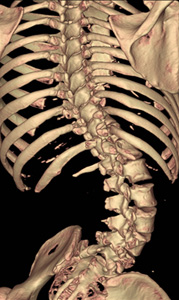

Three-dimension CT scan of the spine showing a hemi vertebra

3차완 CT 영상 검사 상 반척추 형태